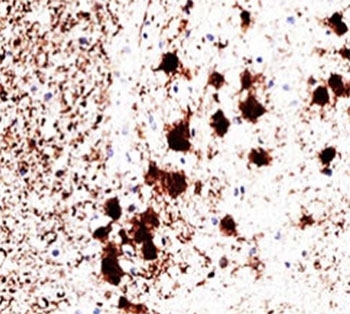

PGP9.5 antibody clone 31A3 is a monoclonal antibody specific for protein gene product 9.5, also known as ubiquitin carboxyl-terminal hydrolase L1. PGP9.5 is a neuron-specific protein with dual roles as a ubiquitin hydrolase and ligase, contributing to protein turnover and cellular homeostasis. It is abundantly expressed in neurons and neuroendocrine cells, making it a highly sensitive and specific marker for nervous system studies. NSJ Bioreagents provides PGP9.5 antibody clone 31A3 for use in neuroscience, developmental biology, and neuropathology.

PGP9.5 antibody clone 31A3 produces strong cytoplasmic and nuclear staining in neuronal populations throughout the central and peripheral nervous systems. It is commonly used to map neuronal networks, trace axonal pathways, and characterize neuroendocrine tissues. In neuropathology, clone 31A3 serves as a gold standard marker for identifying neurons in tissue sections, especially in cases where other neuronal markers may be less robust.